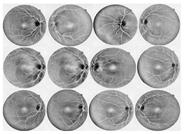

Initially, human experts primarily used digital retinal images in ophthalmic clinics to identify DR and related eye diseases. The retinal blood vessels are important diagnostic indicators for DR and the pathologies of systems within the human eye. More and more research indicate that the accurate extraction of retinal blood vessels is helpful in the analysis of other related ophthalmic diseases. The manual extraction of blood vessels requires an expert ophthalmologist’s skills. Although such manual extraction is possible, it is time-consuming and there can be human error when working with large image datasets. Therefore, automated systems for the precise extraction of retinal blood vessels are urgently needed to reduce the workload of expert ophthalmologists. An example of the automatic extraction of blood vessels is illustrated in Figure 1.

Figure 1.

Example of the automated segmentation and extraction of blood vessels using Weighted Kernel Fuzzy C-Means Clustering and Dilation-Based Function.

Considering the typical retinal blood vessels and the background region information in the digital retinal images shown in Figure 1, three challenges make the retinal vessel-extraction task difficult: